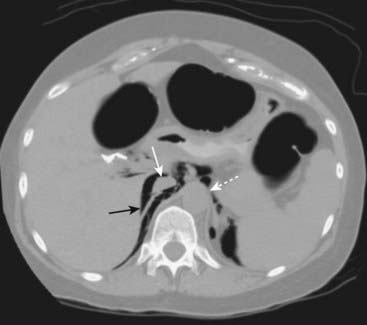

Figure 15-10 Extraperitoneal air seen on CT.

Air is seen in the retroperitoneum (solid black arrow) on this axial CT scan of the upper abdomen. Air outlines the inferior vena cava (solid white arrow) and the aorta (dotted white arrow). Unlike free air, extraperitoneal air is streaky, relatively fixed in position, and outlines extraperitoneal structures such as the vena cava, aorta, psoas muscles, and kidneys.